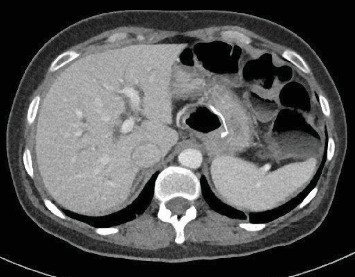

This is a case report of an alternate laparoscopic reconstruction possibility in a patient that required a cephalic duodenopancreatectomy (DPC) who previously underwent a Roux-en-Y gastric bypass (RYGB). The question of what type of reconstruction is to be performed in such patients is thoroughly debated in this article.